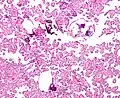

Histopathology

The tumor is neuroectodermal in origin and similar in structure to a normal choroid plexus. They may be created by epithelial cells of the choroid plexus. Papillary fronds lined by bland columnar epithelium are visible under the microscope. Normal absences include mitotic activity, nuclear pleomorphism, and necrosis.[10] Tumors have positive immunohistochemistry for cytokeratin, vimentin, podoplanin, and S-100.[11] Up to 20% of choroid plexus papilloma patients may test positive for glial fibrillary acidic protein (GFAP).[12] Studies have found that fourth ventricle cancers express more S100 than lateral ventricle tumors, and older patients (over 20 years) express more GFAP and transthyretin than younger patients.[13] Some individuals with choroid plexus papilloma have germline TP53 gene mutations, according to genetic analyses.[14] These cancers rarely exhibit nuclear p53 protein positivity. Aicardi syndrome, hypomelanosis of Ito, and 9p duplication are syndromic correlations of choroid plexus papilloma.

Micrograph of a choroid plexus papilloma. H&E stain. -